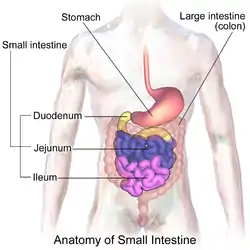

Diagram showing the small intestine and surrounding structures | |

The small intestine or small bowel is an organ in the gastrointestinal tract where most of the absorption of nutrients from food takes place. It lies between the stomach and large intestine, and receives bile and pancreatic juice through the pancreatic duct to aid in digestion. The small intestine is about 5.5 metres (18 feet) long and folds many times to fit in the abdomen. Although it is longer than the large intestine, it is called the small intestine because it is narrower in diameter.

The small intestine has three distinct regions – the duodenum, jejunum, and ileum. The duodenum, the shortest, is where preparation for absorption through small finger-like protrusions called villi begins.[2] The jejunum is specialized for the absorption through its lining by enterocytes: small nutrient particles which have been previously digested by enzymes in the duodenum. The main function of the ileum is to absorb vitamin B12, bile salts, and whatever products of digestion that were not absorbed by the jejunum.

Parts

The small intestine is divided into three structural parts.

- The duodenum is a short structure ranging from 20–25 cm (8–10 in) in length, and shaped like a "C".[12] It surrounds the head of the pancreas. It receives gastric chyme from the stomach, together with digestive juices from the pancreas (digestive enzymes) and the liver (bile). The digestive enzymes break down proteins and bile emulsifies fats into micelles. The duodenum contains Brunner's glands, which produce a mucus-rich alkaline secretion containing bicarbonate. These secretions, in combination with bicarbonate from the pancreas, neutralize the stomach acids contained in gastric chyme.

- The jejunum is the midsection of the small intestine, connecting the duodenum to the ileum. It is about 2.5 m (8 ft) long, and contains the circular folds, and intestinal villi that increase its surface area. Products of digestion (sugars, amino acids, and fatty acids) are absorbed into the bloodstream here. The suspensory muscle of duodenum marks the division between the duodenum and the jejunum.

- The ileum: The final section of the small intestine. It is about 3 m long, and contains villi similar to the jejunum. It absorbs mainly vitamin B12 and bile acids, as well as any other remaining nutrients. The ileum joins to the cecum of the large intestine at the ileocecal junction.